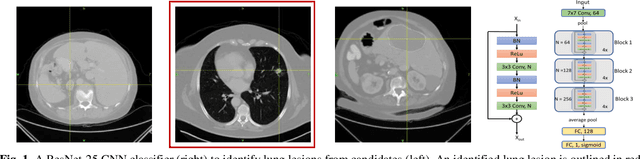

Abstract:Herein we propose a deep learning-based approach for the prediction of lung lesion response based on radiomic features extracted from clinical CT scans of patients in non-small cell lung cancer trials. The approach starts with the classification of lung lesions from the set of primary and metastatic lesions at various anatomic locations. Focusing on the lung lesions, we perform automatic segmentation to extract their 3D volumes. Radiomic features are then extracted from the lesion on the pre-treatment scan and the first follow-up scan to predict which lesions will shrink at least 30% in diameter during treatment (either Pembrolizumab or combinations of chemotherapy and Pembrolizumab), which is defined as a partial response by the Response Evaluation Criteria In Solid Tumors (RECIST) guidelines. A 5-fold cross validation on the training set led to an AUC of 0.84 +/- 0.03, and the prediction on the testing dataset reached AUC of 0.73 +/- 0.02 for the outcome of 30% diameter shrinkage.